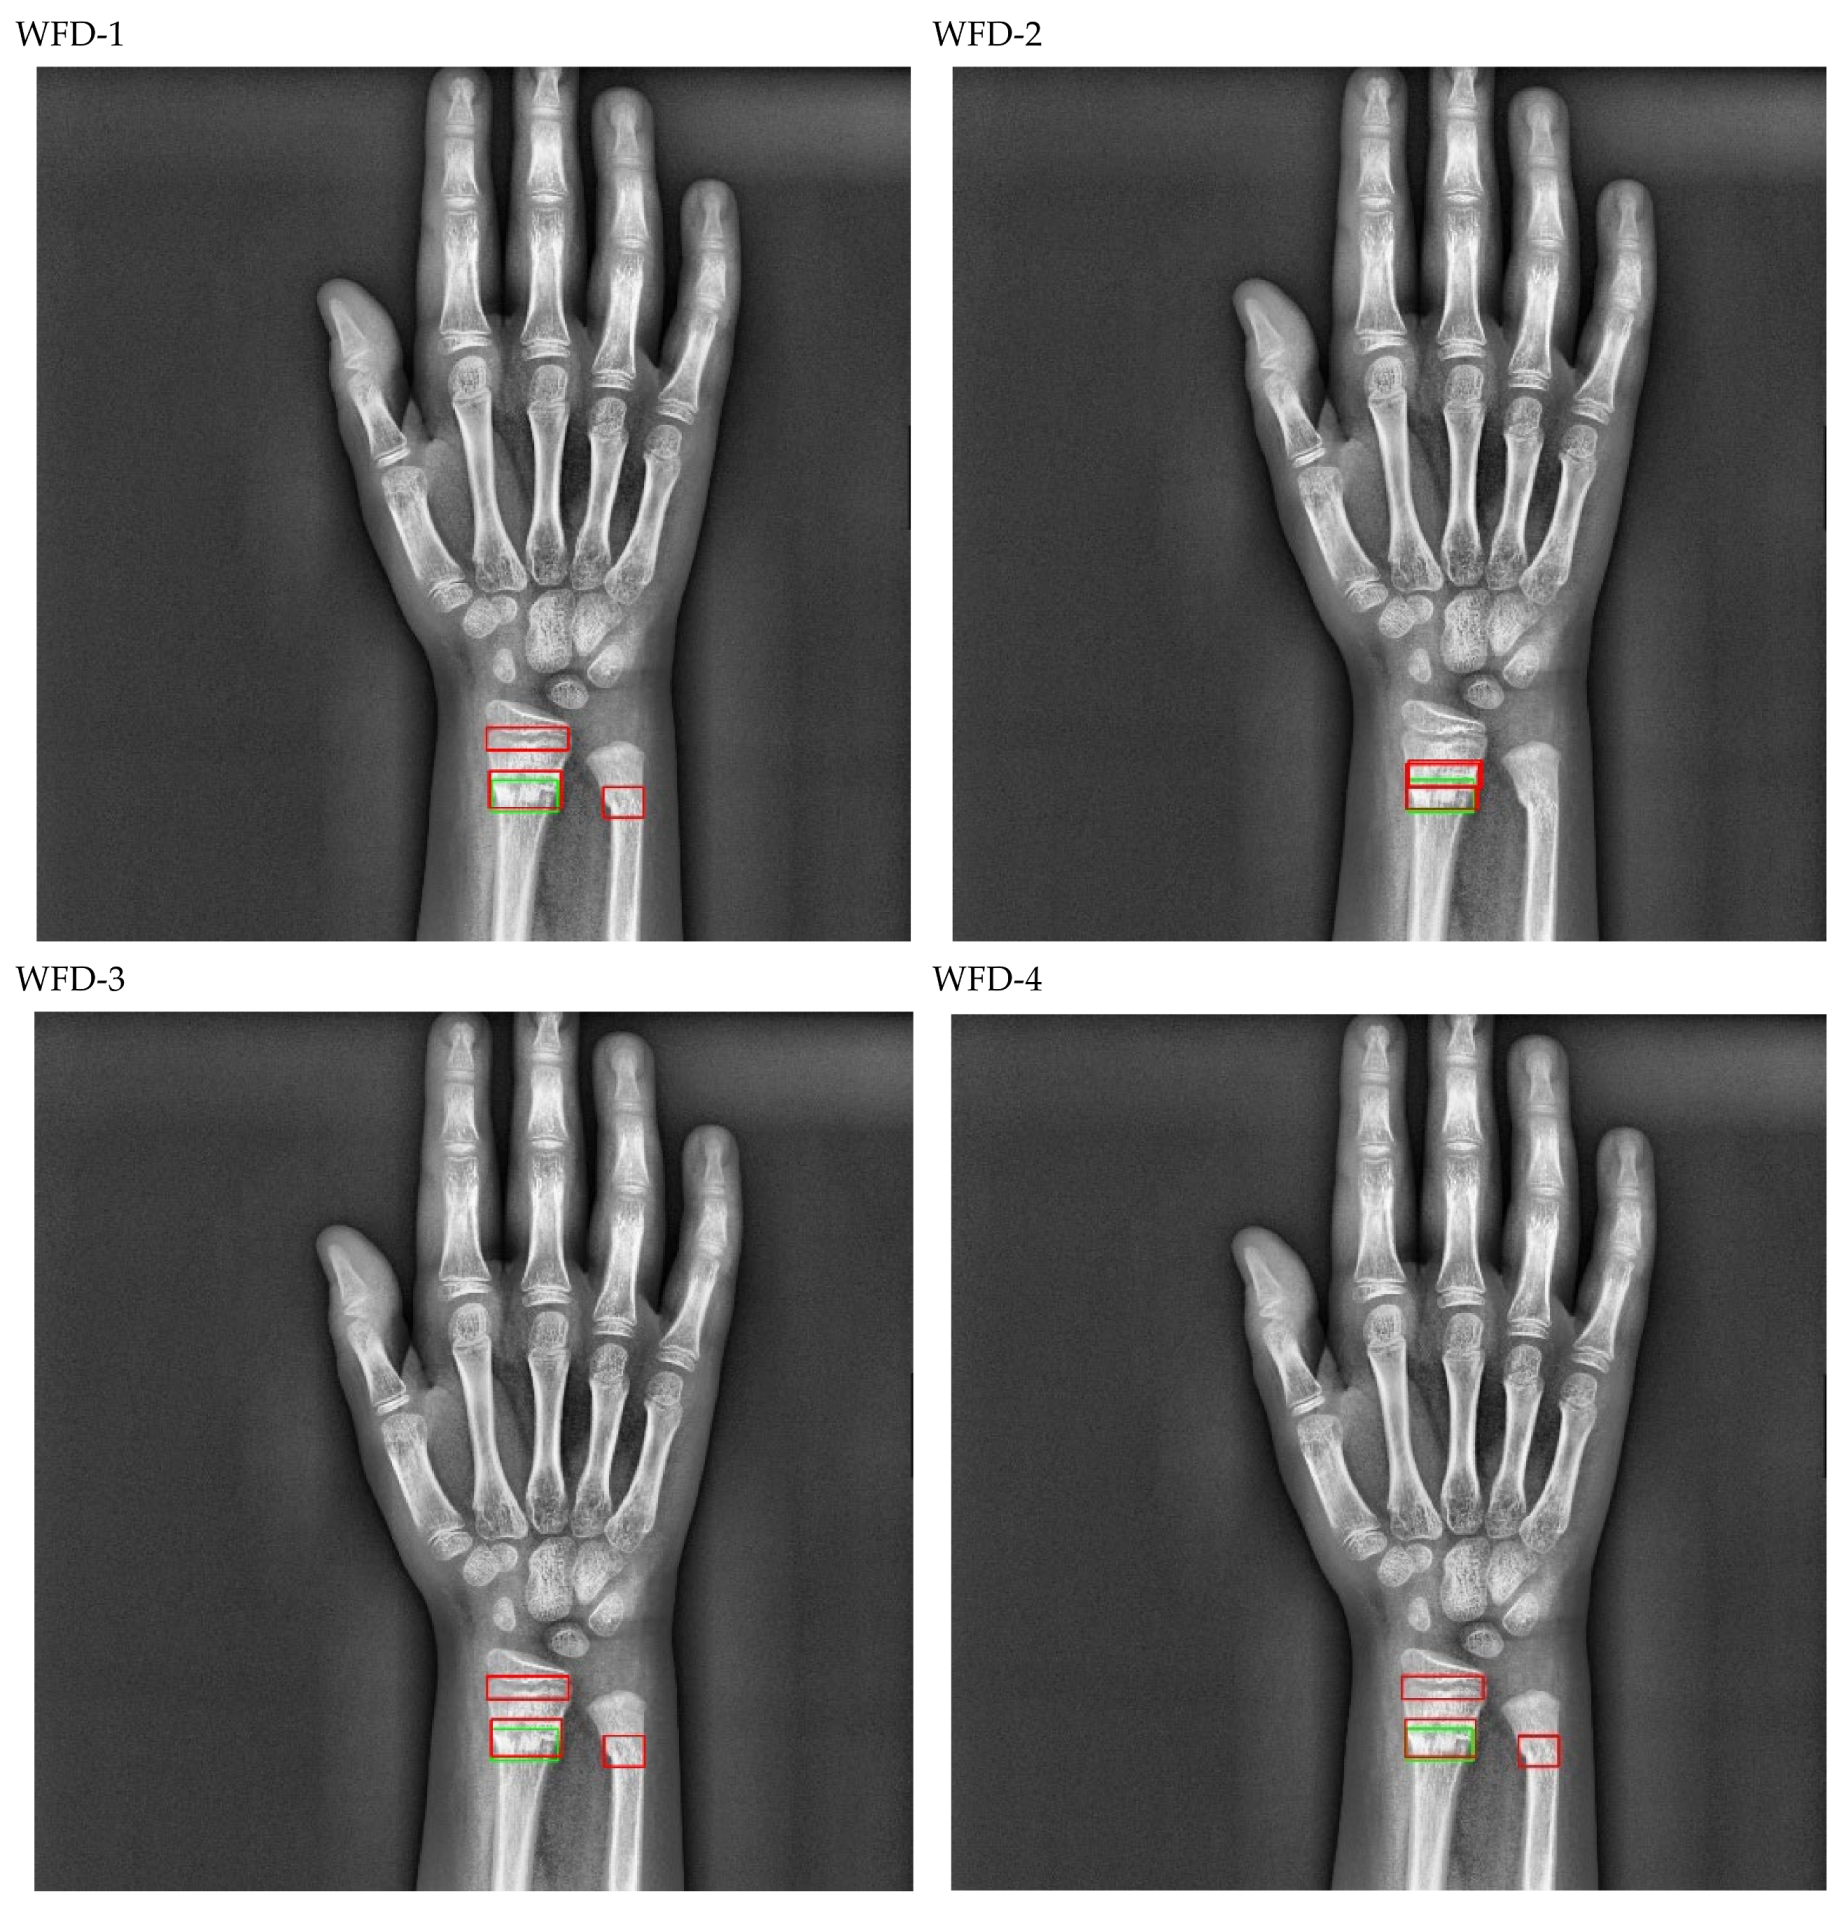

The bounding box outputs achieved from the fracture detection performed with the PAA model with the best AP50 score are displayed in Figure 17 for right/left hand as a sample in the dataset, and the precision-recall graph is provided in Figure 18.

Figure 17.

Sample of left/right wrist fracture results [ground-truth bounding box (green), predicted bounding box (red)] for PAA (Best score of 20 models).

Figure 18.

Precision-recall curve of PAA (best score of 20 models).